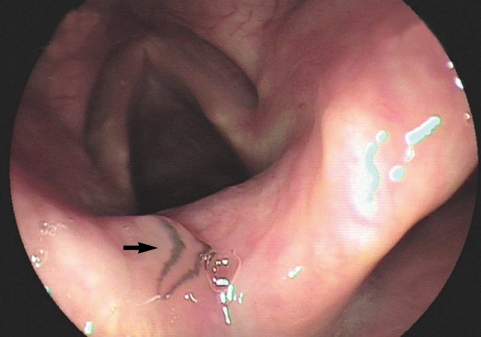

During a drug-induced sleep endoscopy for the upper airway and esophagus evaluation, a motile fluke was found attached to the surface of the arytenoid region (Fig. 1). The worm moving its posterior portion of the body peristaltically was immediately removed from the mucosa. It was partially torn at the lateral part of the middle one third when it was grasped by endoscopic forceps (Fig. 2). After removal of the worm, petechial hemorrhage was observed on the affected mucosa. The pain and other symptoms were gradually relieved. In unfixed condition, the fluke was 5.25 mm in length, 1.81 mm in maximum width at the posterior one third of the body. The oral sucker was located near the frontal end of the body. The ventral sucker was large and situated at the middle of the anterior one third of the body. The intestine of the worm was heavily dark due to ingested materials at its middle and posterior one third portion.

Fig. 1

Photographs of the whole worm of Clinostomum complanatum. Endoscopic image showing the parasitic fluke (arrow) attached to the arytenoid region of the larynx.

Fig. 1 Photographs of the whole worm of Clinostomum complanatum. Endoscopic image showing the parasitic fluke (arrow) attached to the arytenoid region of the larynx.